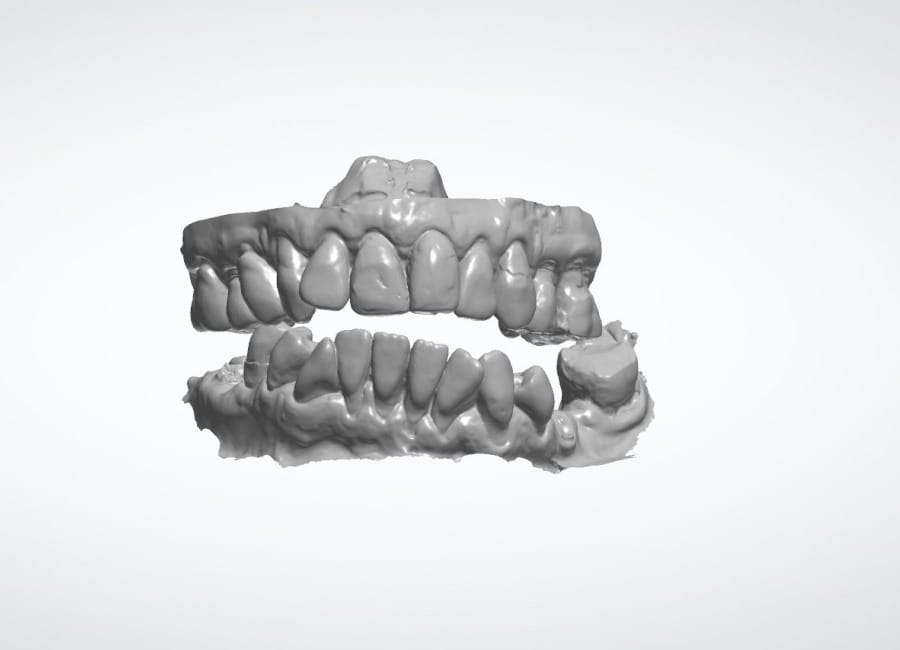

Alongside this, a digital intraoral scan and detailed photographic records were captured. These provided accurate models of her teeth and bite, as well as valuable information about facial proportions and smile aesthetics. Together, these records ensured that planning would address both the functional and cosmetic aspects of her rehabilitation.

All data were transferred into digital treatment planning software, allowing virtual placement of implants and collaboration with the dental laboratory before surgery. This enabled careful evaluation of long-term outcomes and ensured the design of provisional and final prosthetics could be completed with precision. Following these discussions, the decision was made to proceed with the Fixed-Teeth-in-a-Day approach using the All-on-4 technique.